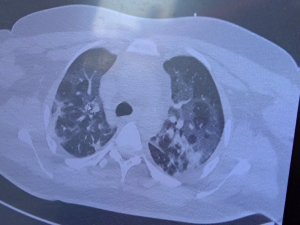

Aydın’da vaka sayıları artmaya devam ediyor